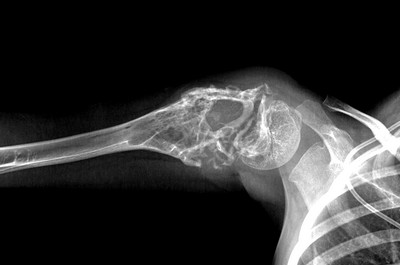

Рентгенологические признаки саркомы Юинга:

- поражение кости без четких границ, так называемый симптом «изъеденная молью», чаще распространяется по костномозговому каналу;

- «луковичный периостит» – многослойный периостит, сочетающийся с игольчатым;

- наличие мягкотканного компонента однородной структуры;

- в 5% случаев встречается патологический перелом.